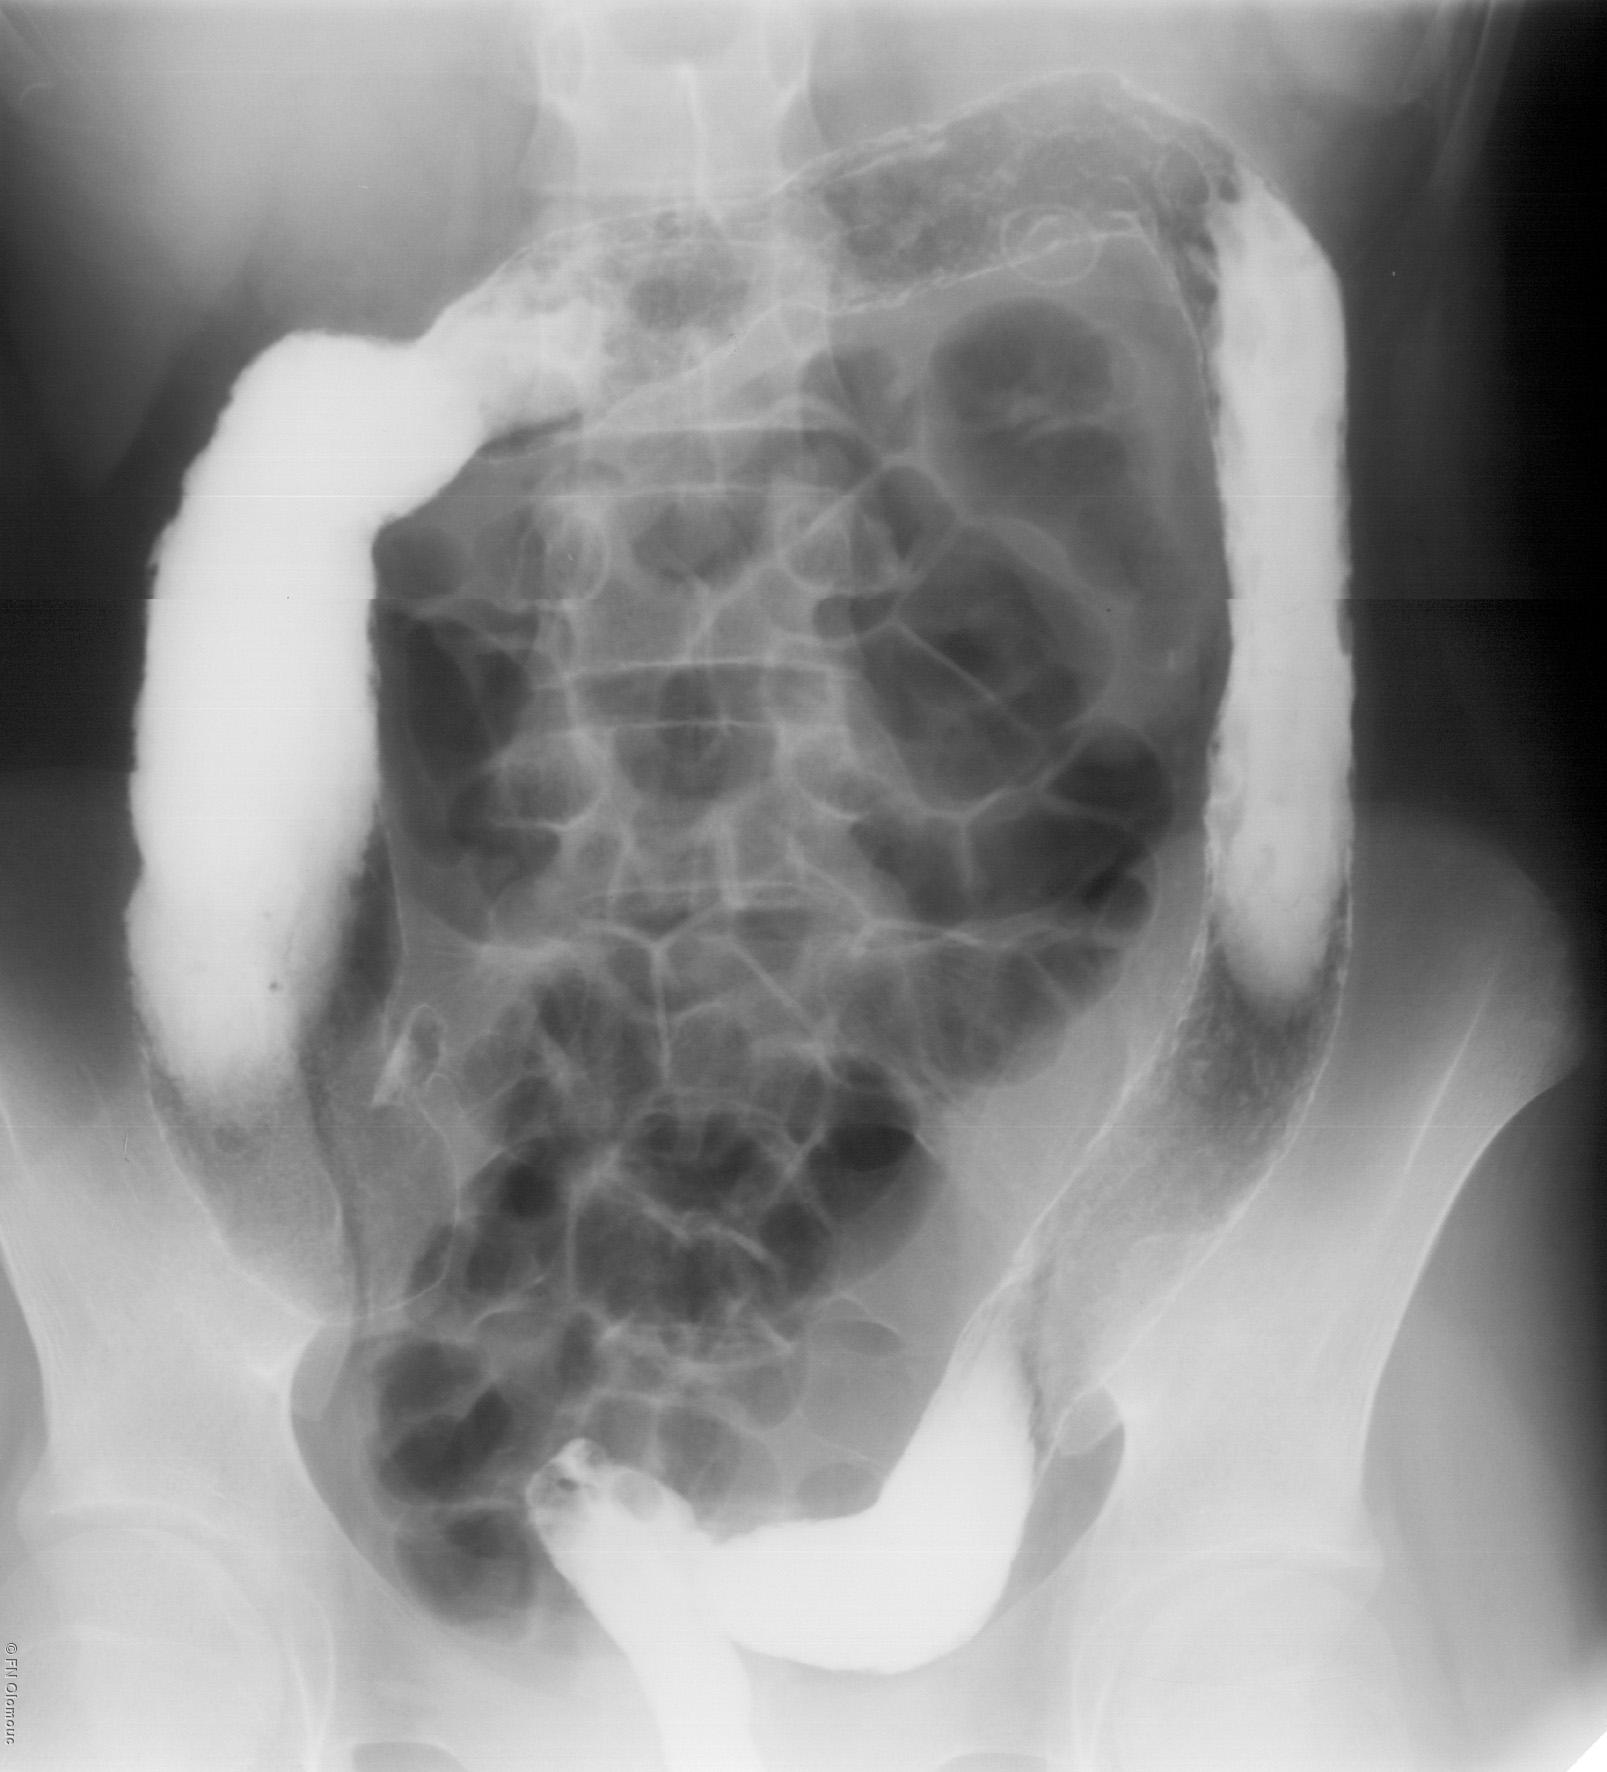

Kontrastní vyšetření tlustého střeva (irrigografie)

Kontrastní vyšetření tlustého střeva (irrigografie).